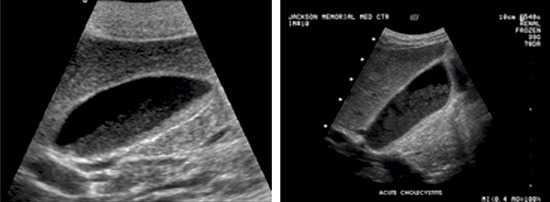

Осадок в желчном пузыре может иметь различные формы, и его тип можно определить с помощью ультразвукового исследования. Сладж-синдром приводит к следующим изменениям в желчи:

| Диагностика | УЗИ органов брюшной полости (наиболее информативный метод), реже – МРТ, КТ. | Показывает, как будет подтвержден диагноз. |

Симптомы и диагностика: Билиарный сладж может не вызывать никаких симптомов, но в некоторых случаях он может приводить к болям в правом подреберье, тошноте и другим диспепсическим расстройствам. Для его диагностики часто используется ультразвуковое исследование, которое позволяет визуализировать наличие сладжа в желчном пузыре.

При возникновении болезненных ощущений как у взрослых, так и у детей, для диагностики заболевания в первую очередь назначают ультразвуковое исследование. УЗИ желчного пузыря позволяет выявить наличие осадка и определить его форму. В дополнение могут использоваться магнитно-резонансная томография и забор желчи с помощью дуоденального зондирования.